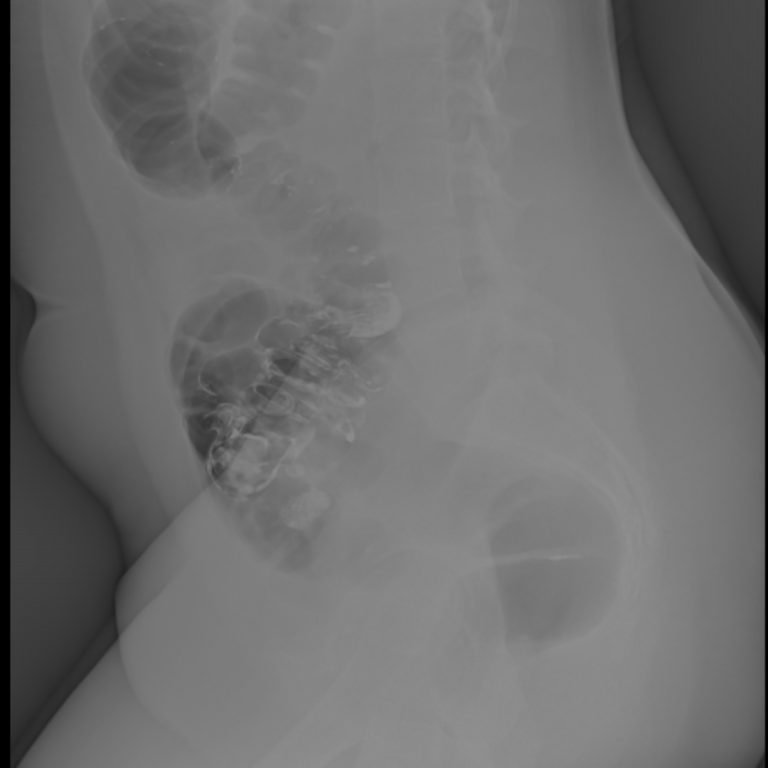

IVP- İNTRAVENÖZ PYELOGRAM

IVP böbrek inceleme filmi, böbrek ve idrar yolları hastalıklarının tanısında başvurulan radyolojik bir inceleme yöntemidir. Bu inceleme Merkezimizde,son sistem C kollu dijital röntgen cihazyla. bu alanda uzmanlık eğitimi almış hekimlerimiz tarafından yapılmaktadır.Böbrekler ve idrar yolları, karın içi organları (özellikle barsaklar) tarafından örtüldüklerinden röntgen filmlerinde net izlenemezler. Onları net olarak görüntüleyebilmek için incelemeye gelmeden önce barsaklarınızın boşaltılması amacı ile önceden “müshil” adı ile tanıdığımız bir ilaç kullanmanız gerekmektedir.Bu amaçla inceleme randevunuzdan önce size tarif edildiği şekilde hazırlığınızı yaptıktan sonra hiçbir şey yemeyerek merkezimize aç karnına gelmelisiniz.

Içecek olduğunuz müshil ilacı sizi geçici olarak ishal yaparak barsaklarınızın boşalmasını sağlayacaktır. Ilaç, etkisini genellikle 8-10 saat içinde göstereceğinden size bildirilen dozların dışına çıkmamanızı öneririz. IVP filminde; böbreklerinizin ve idrar kollarınızın görüntülenmesi amacı ile “Radyolojik Kontrast Ilaçlar” adını verdiğimiz bir ilacın damar yolu ile enjeksiyonu gerekmektedir. Bu ilaçlar “iyot” içerirler ve kana karıştıktan sonra böbrekler tarafından süzülerek, röntgen filminde böbrek ve idrar yollarının görüntülenmesini sağlarlar.

- Sol üreter distal orifis düzeyine superpoze yaklaşık 5 mm çapındaki opasite kalkül açısından anlamlı bulunmuştur. Bunun sonucu geç fazda sol üreter distal 1/3 segmenti vizualize olmuştur ve normalden hafif geniştir. Bununla birlikte sol proksimal üreter ve sol renal pelvikaliksiyel sisteminde patolojik ektazi izlenmemiştir. Bulgular parsiyel obstrüksiyona yol açan üreter orifis kalkülü açısından anlamlı bulunmuştur.

- Sol böbrek orta ve alt kaliksiyel yapılarda sırasıyla 3 mm ve 3.5 mm boyutlarında 2 adet nonobstrüktif kalkül mevcuttur.